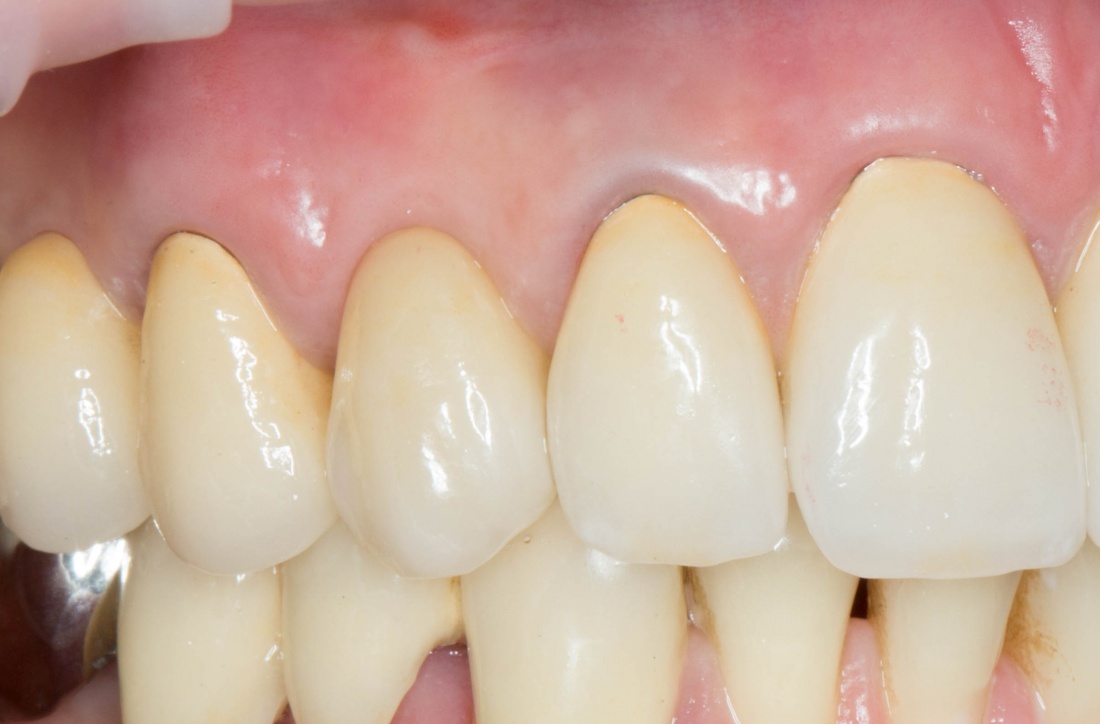

Рекомендации по установке имплантов. Для всех. Часть V.